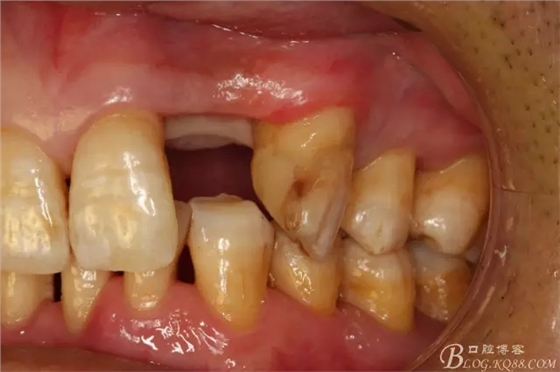

圖3.術(shù)前口內(nèi)照片:正面觀閉口位

圖4.左側(cè)側(cè)面觀,22間隙正常,23近中輕度扭轉(zhuǎn)